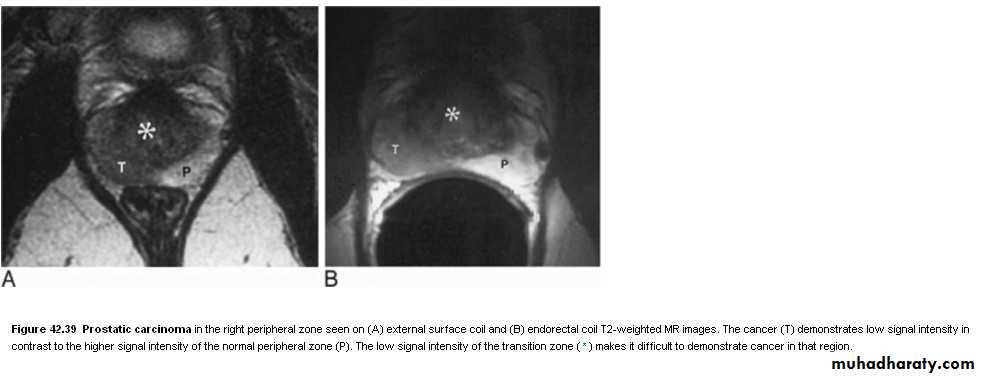

• MRI: the zonal anatomy of prostate is very well demonstated by MRI. In T2 images, the peripheral zone(the most common origin of tumors) is of high signal intensity and the tumor is of low signal intensity. MRI is used to assess early stage prostatic cancer in patients being considered for radical surgery or radiotherapy. MRI is also used to demonstrate extracapsular tumor spread, to show invasion of the seminal vesicles, and to demonstrate possible LN metastases.